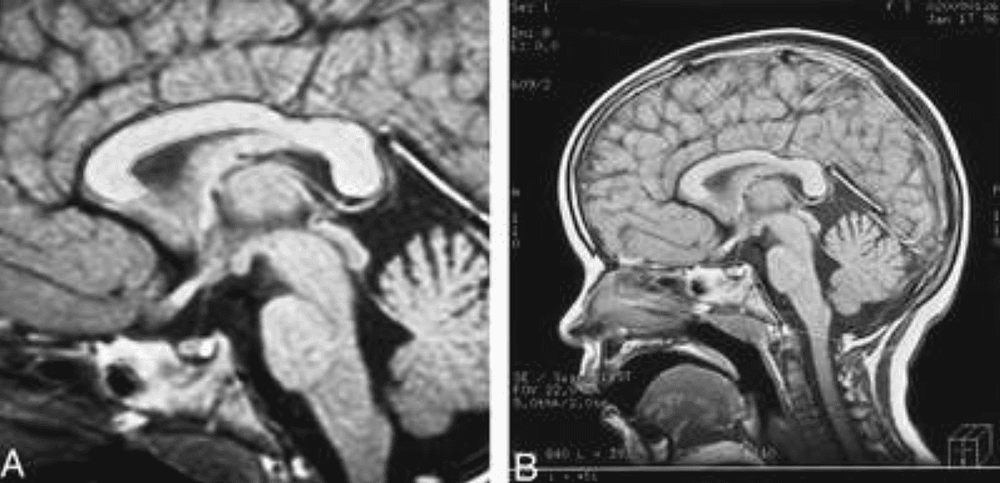

- Dị dạng não, dị dạng màng não, dị dạng sọ: dị dạng não trước, dị nguyên, u mỡ, u quái, Chiari. Nang màng nhện, thoát vị não màng não. Dính liền khớp sọ.